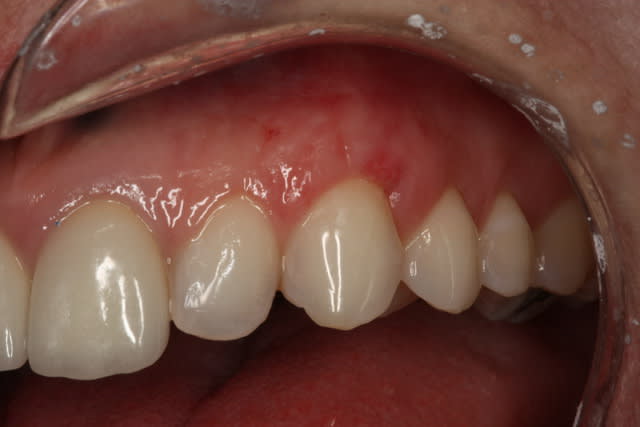

Tient, un suivi de 24 mois post greffe sur 2 implants

Mec de 60 ans

Un petit hop sur le 1er cas du fil

1- Pré-op

2- J+14

3- J+14

4- J+3 mois

--